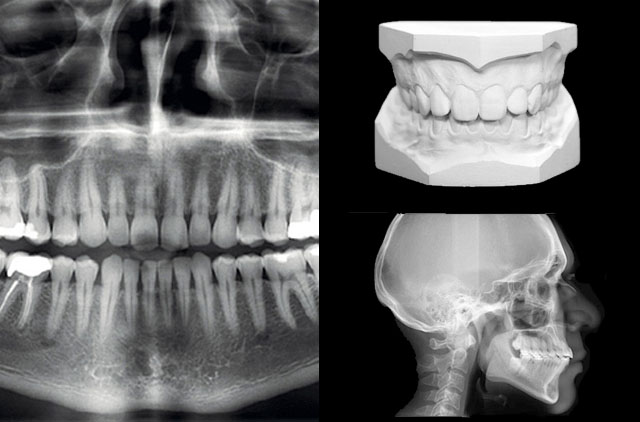

Estudio Convencional

-Panoramica (OP)

-Lateral de Craneo (LC) 8 x 10¨

-Modelos de Estudio en yeso con caja plática rígida

Estudio completo de ortodoncia en 3D (cone-beam) digital CD

-Lateral de Craneo (LC)

-Trazos Cefalométricos, tomografía volumétrica cone-beam